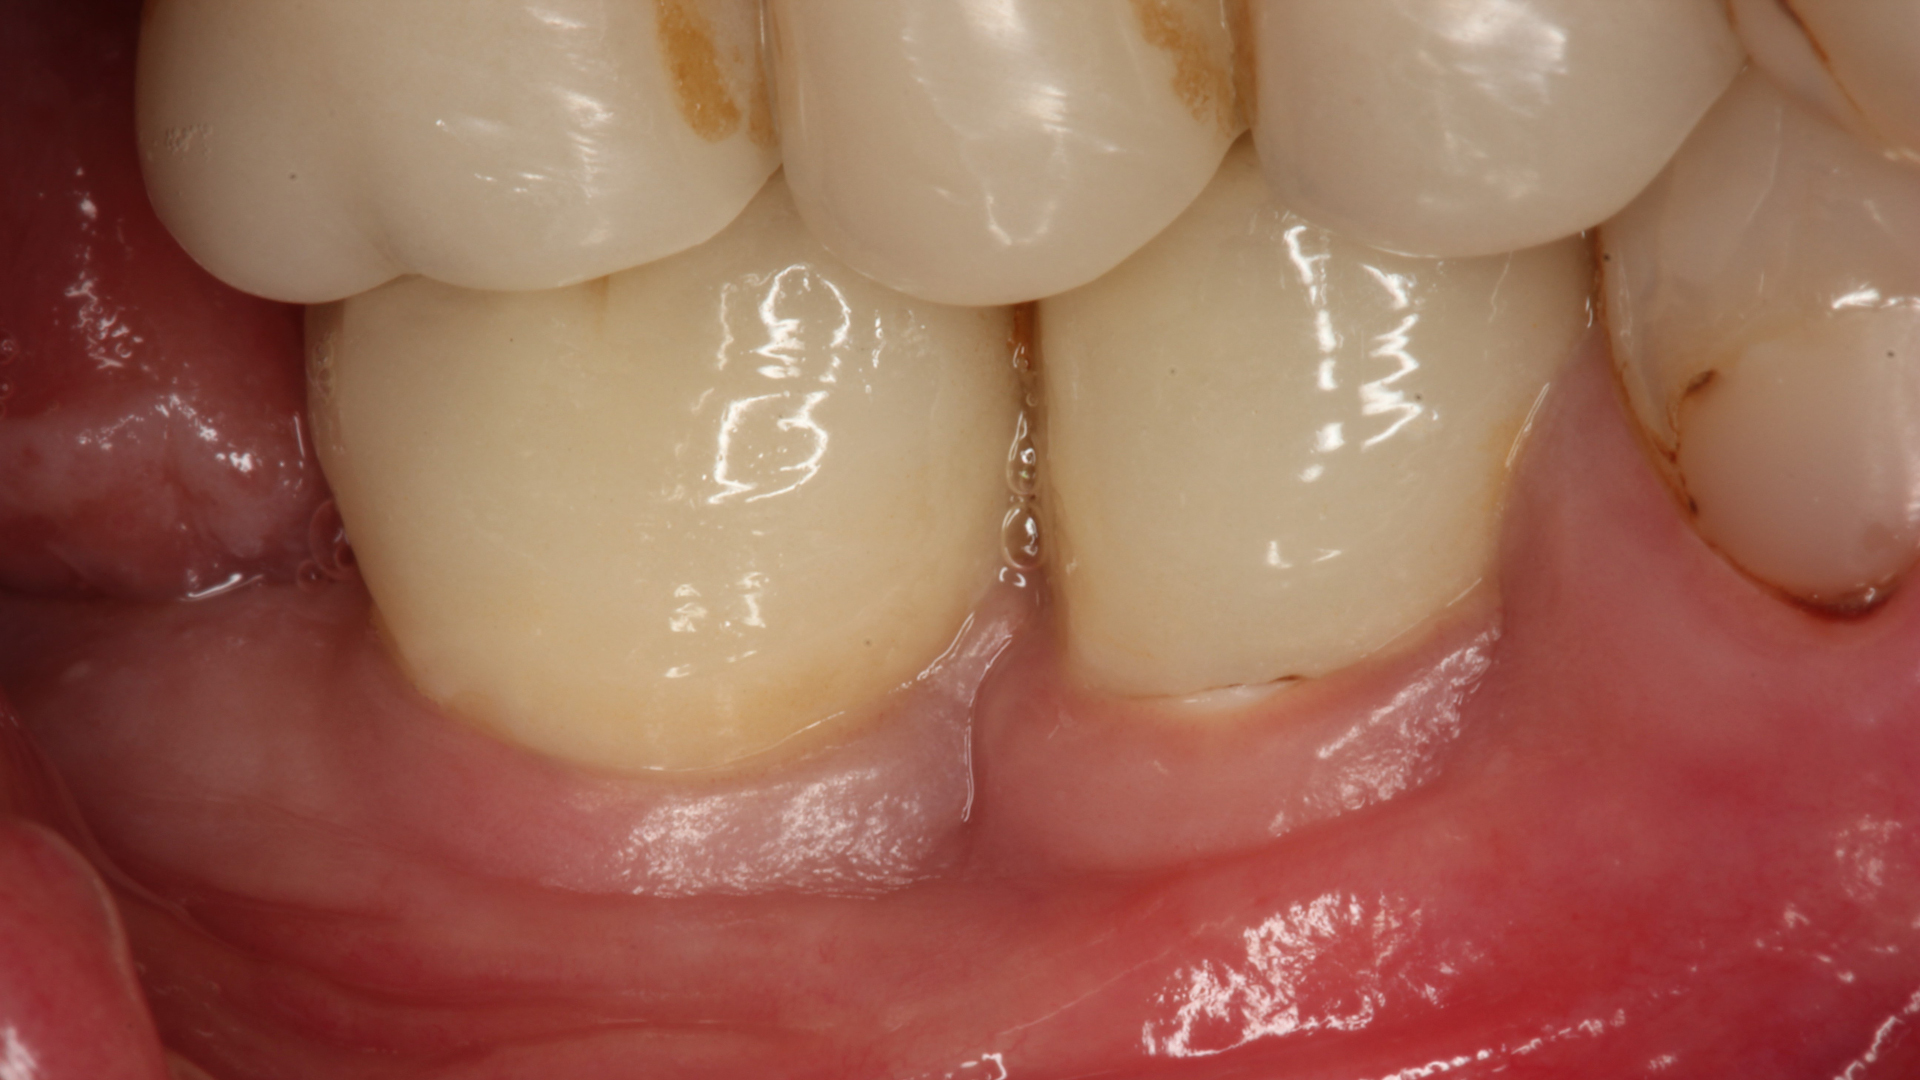

ZURICH, Switzerland: At a press event in Zurich on 15 February, Dr Roland Glauser, a Zurich-based expert in comprehensive implantology, highlighted peri-implantitis as a primary challenge in implant dentistry, a view supported by leading dental associations. Research shows that nearly half of patients experience peri-implant mucositis, often leading to peri-implantitis, which affects 22% of patients and is a leading cause of implant failure. The two-piece Patent Dental Implant System aims to combat this by preventing chronic tissue inflammation, and it was reported at the briefing that a new study on this zirconia system found no peri-implantitis after up to 12 years, even in compromised patients.

Research shows that nearly half of dental implant patients experience peri-implant mucositis, often leading to peri-implantitis, which affects 22% of patients and is a leading cause of implant failure. (Image: Karapataki et al. 2023)